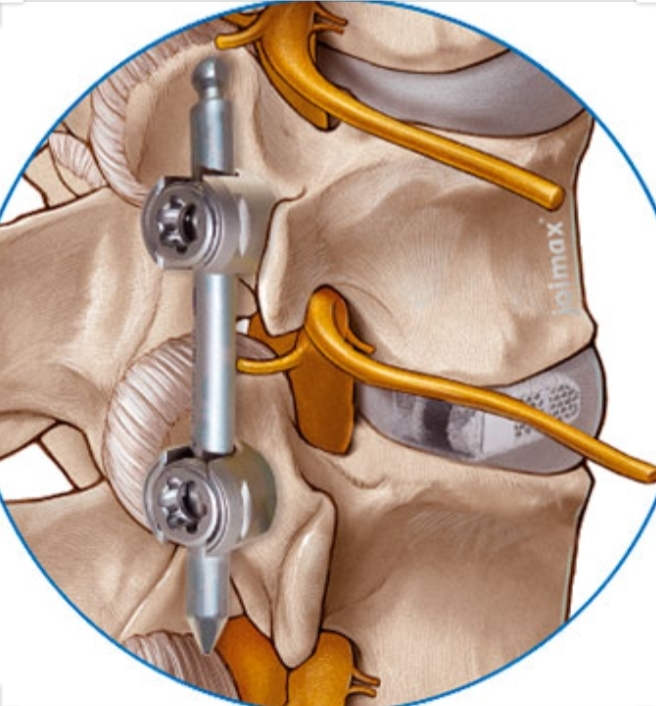

August 2020 ++

und so gehts weiter

so wies aussieht, ist der Nerv, der zu den Beinen führt, in der Wirbelsäule geklemmt.

Es muß also ein Weg gefunden werden, der diese Einengung beseitigt.

Wahrscheinlich muß ich dazu an der Wirbelsäule operiert werden.

Habe ein MRT machen lassen, was das bestätigt.

Die Durchgänge für die Nerven zu den Beinen sind total zugewachsen.

Das soll altersbedingt sein.

Wahrscheinlich hat der Körper im Laufe der Jahre doch etwas zu viel des Guten getan beim Reparieren.